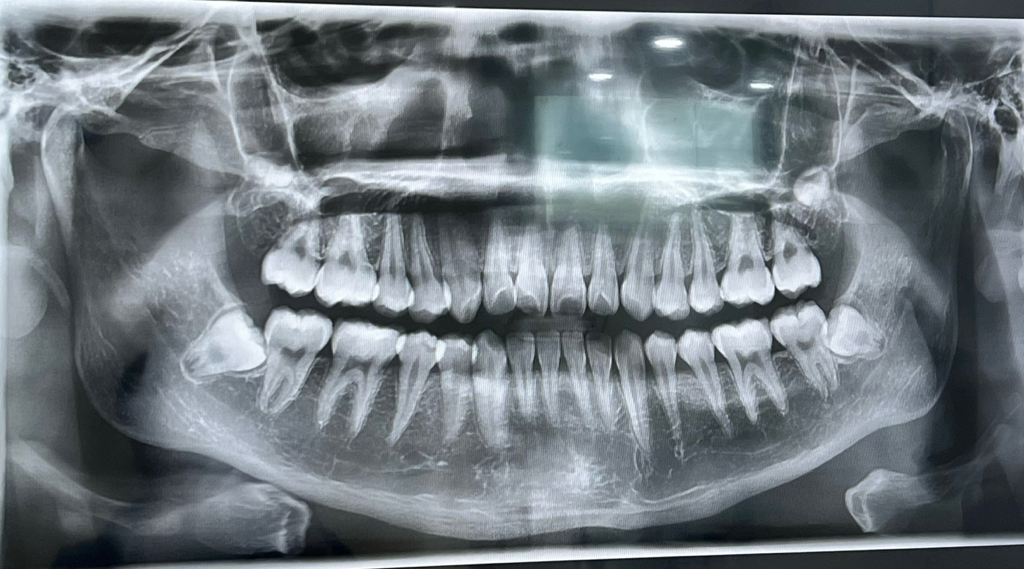

사랑니로 인해 볼에 통증이 나타날수 있습니다. 현재 사진상 사랑니 방향이 앞의 어금니를 상하게 하는 방향으로 있기에 방치시에는 앞의 어금니가 서서히 상해 두개 치아 모두 발치가 필요로 될수 있습니다. 따라서 입대전에 가능한 빠른시일내에 사랑니를 발치하길 권합니다.

대부분 시간이 지나면서 괜찮아지며 사진으로 봤을 때는 완전히 매복되어 있어서 다른 곳에 문제를 발생시킬 가능성이 적습니다.